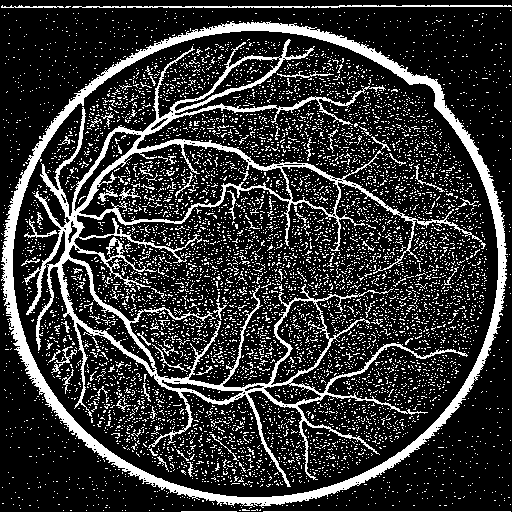

3.1 Vessel Segmentation on DRIVE

We conduct vessel segmentation experiments with DRIVE to evaluate the performance of our proposed STD-Net. The Digital Retinal Images for Vessel Extraction (DRIVE) dataset [19] contains 40 colored fundus images (20 training images and 20 testing images), which are obtained from a diabetic retinopathy screening program in the Netherlands. We resize the original images to 512×512512512512\times 512 as inputs. Following the previous work [20], we employ Specificity (Spe), Sensitivity (Sen), Accuracy (Acc), intersection-over-union(IOU), and Area Under ROC (AUC) as measurements.

Table 1 shows the performances of different methods for DRIVE. Based on the results, for the four metrics AUC, Acc, Sen, and IOU, the proposed STD-Net achieves the highest value. STD-Net outperforms the backbone M-Net by 0.0021, 0.0034, 0.0471 and 0.0269 in terms of Acc, AUC, Sen, and IOU, respectively. Note that the proposed STD-Net achieves a much higher Sen score than M-Net, which shows that our structure-texture demixing mechanism improves the structure detection ability of models.